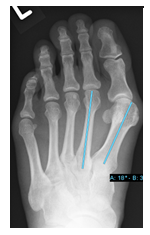

Hallux valgus et rigidus (Zehenballen mit Arthrose)

Diese Fehlstellung im Sinne eines Hallux valgus ist kombiniert mit einer Arthrose des Großzehengrundgelenkes. Genauso wie bei Arthrose ohne Fehlstellung sollte zunächst versucht werden, die Beschwerden mit einer Anpassung des Schuhs und mit Einlagen zu lindern. Wenn hier keine ausreiche

Auf dem Röntgenbild zeigt sich die fortgeschrittene Arthrose des Großzehengrundgelenkes. Der Knorpel ist vollkommen zerstört (Pfeil). Es reibt Knochen auf Knochen, was die Schmerzen verursacht.